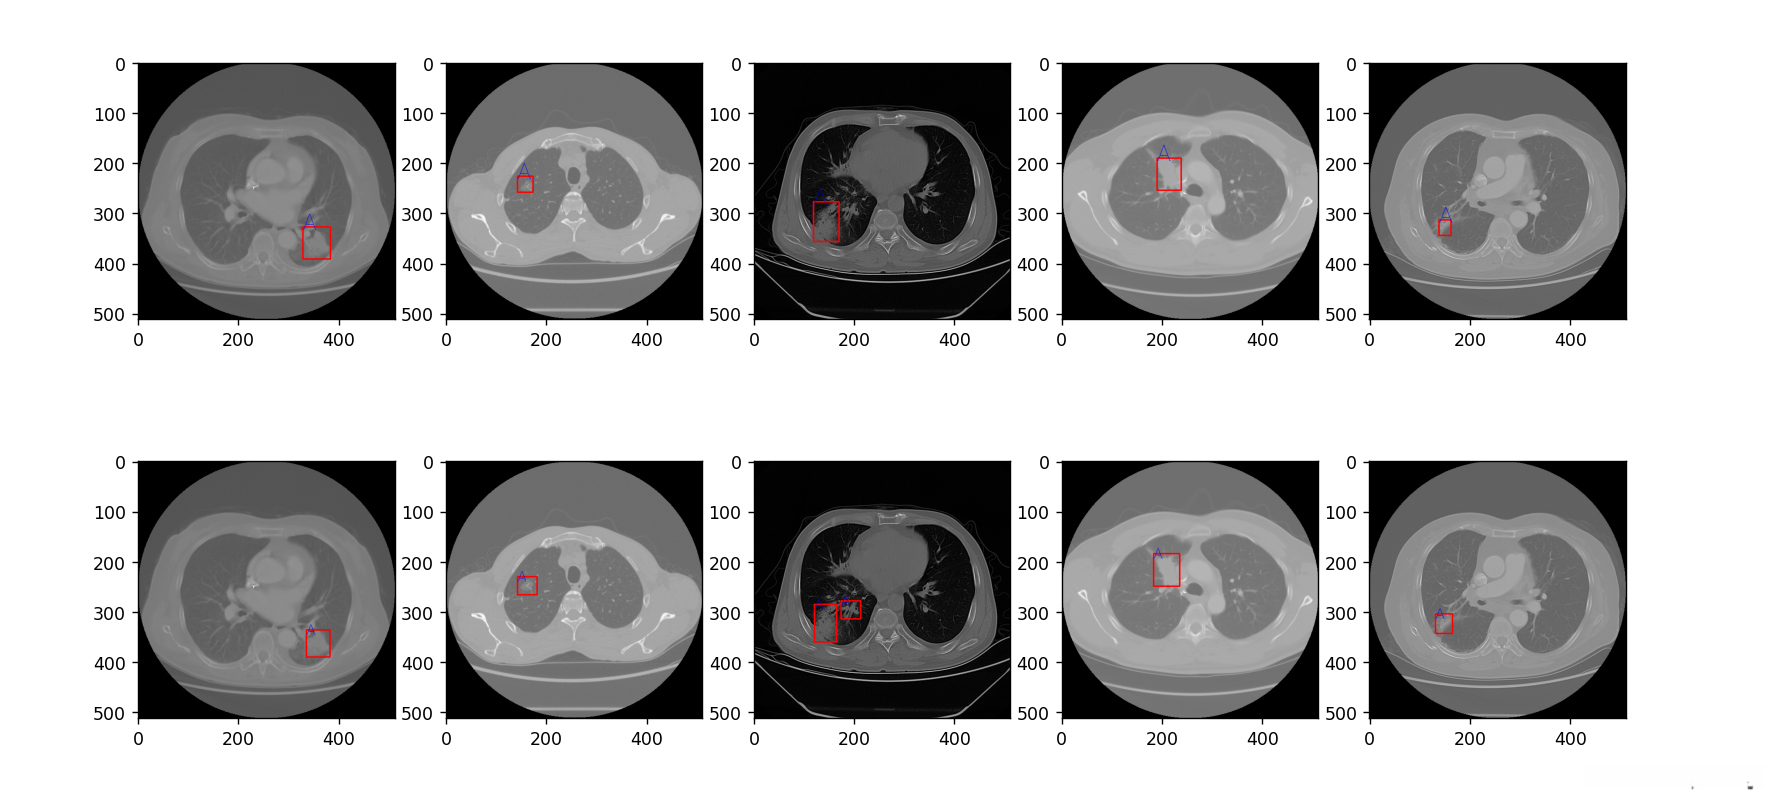

5.2 结果展示

这里呈现的是(训练数据集合)通过以下链接可获得:

第一行为truth,第二行为prediction

该测试集在测试集中的表现较为突出,在评估指标中呈现出良好的效果。

可能因为数据的原因吧,iou虽然不高,但是在testSet 的表现也比较好